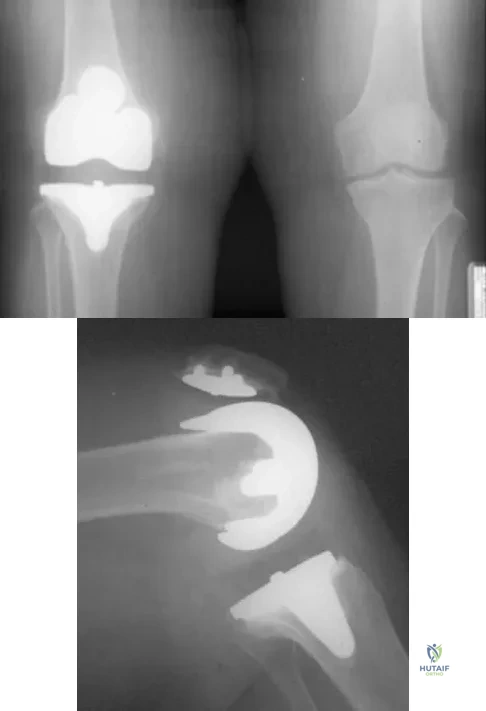

A 63-year-old woman reports giving way of the knee and pain after undergoing primary total knee arthroplasty (TKA) 1 year ago. Examination reveals that the knee is stable in full extension but has gross anteroposterior instability at 90 degrees of flexion. The patient can fully extend her knee with normal quadriceps strength. Studies for infection are negative. AP and lateral radiographs are shown in Figures 12a and 12b, respectively. What is the appropriate management?

Explanation